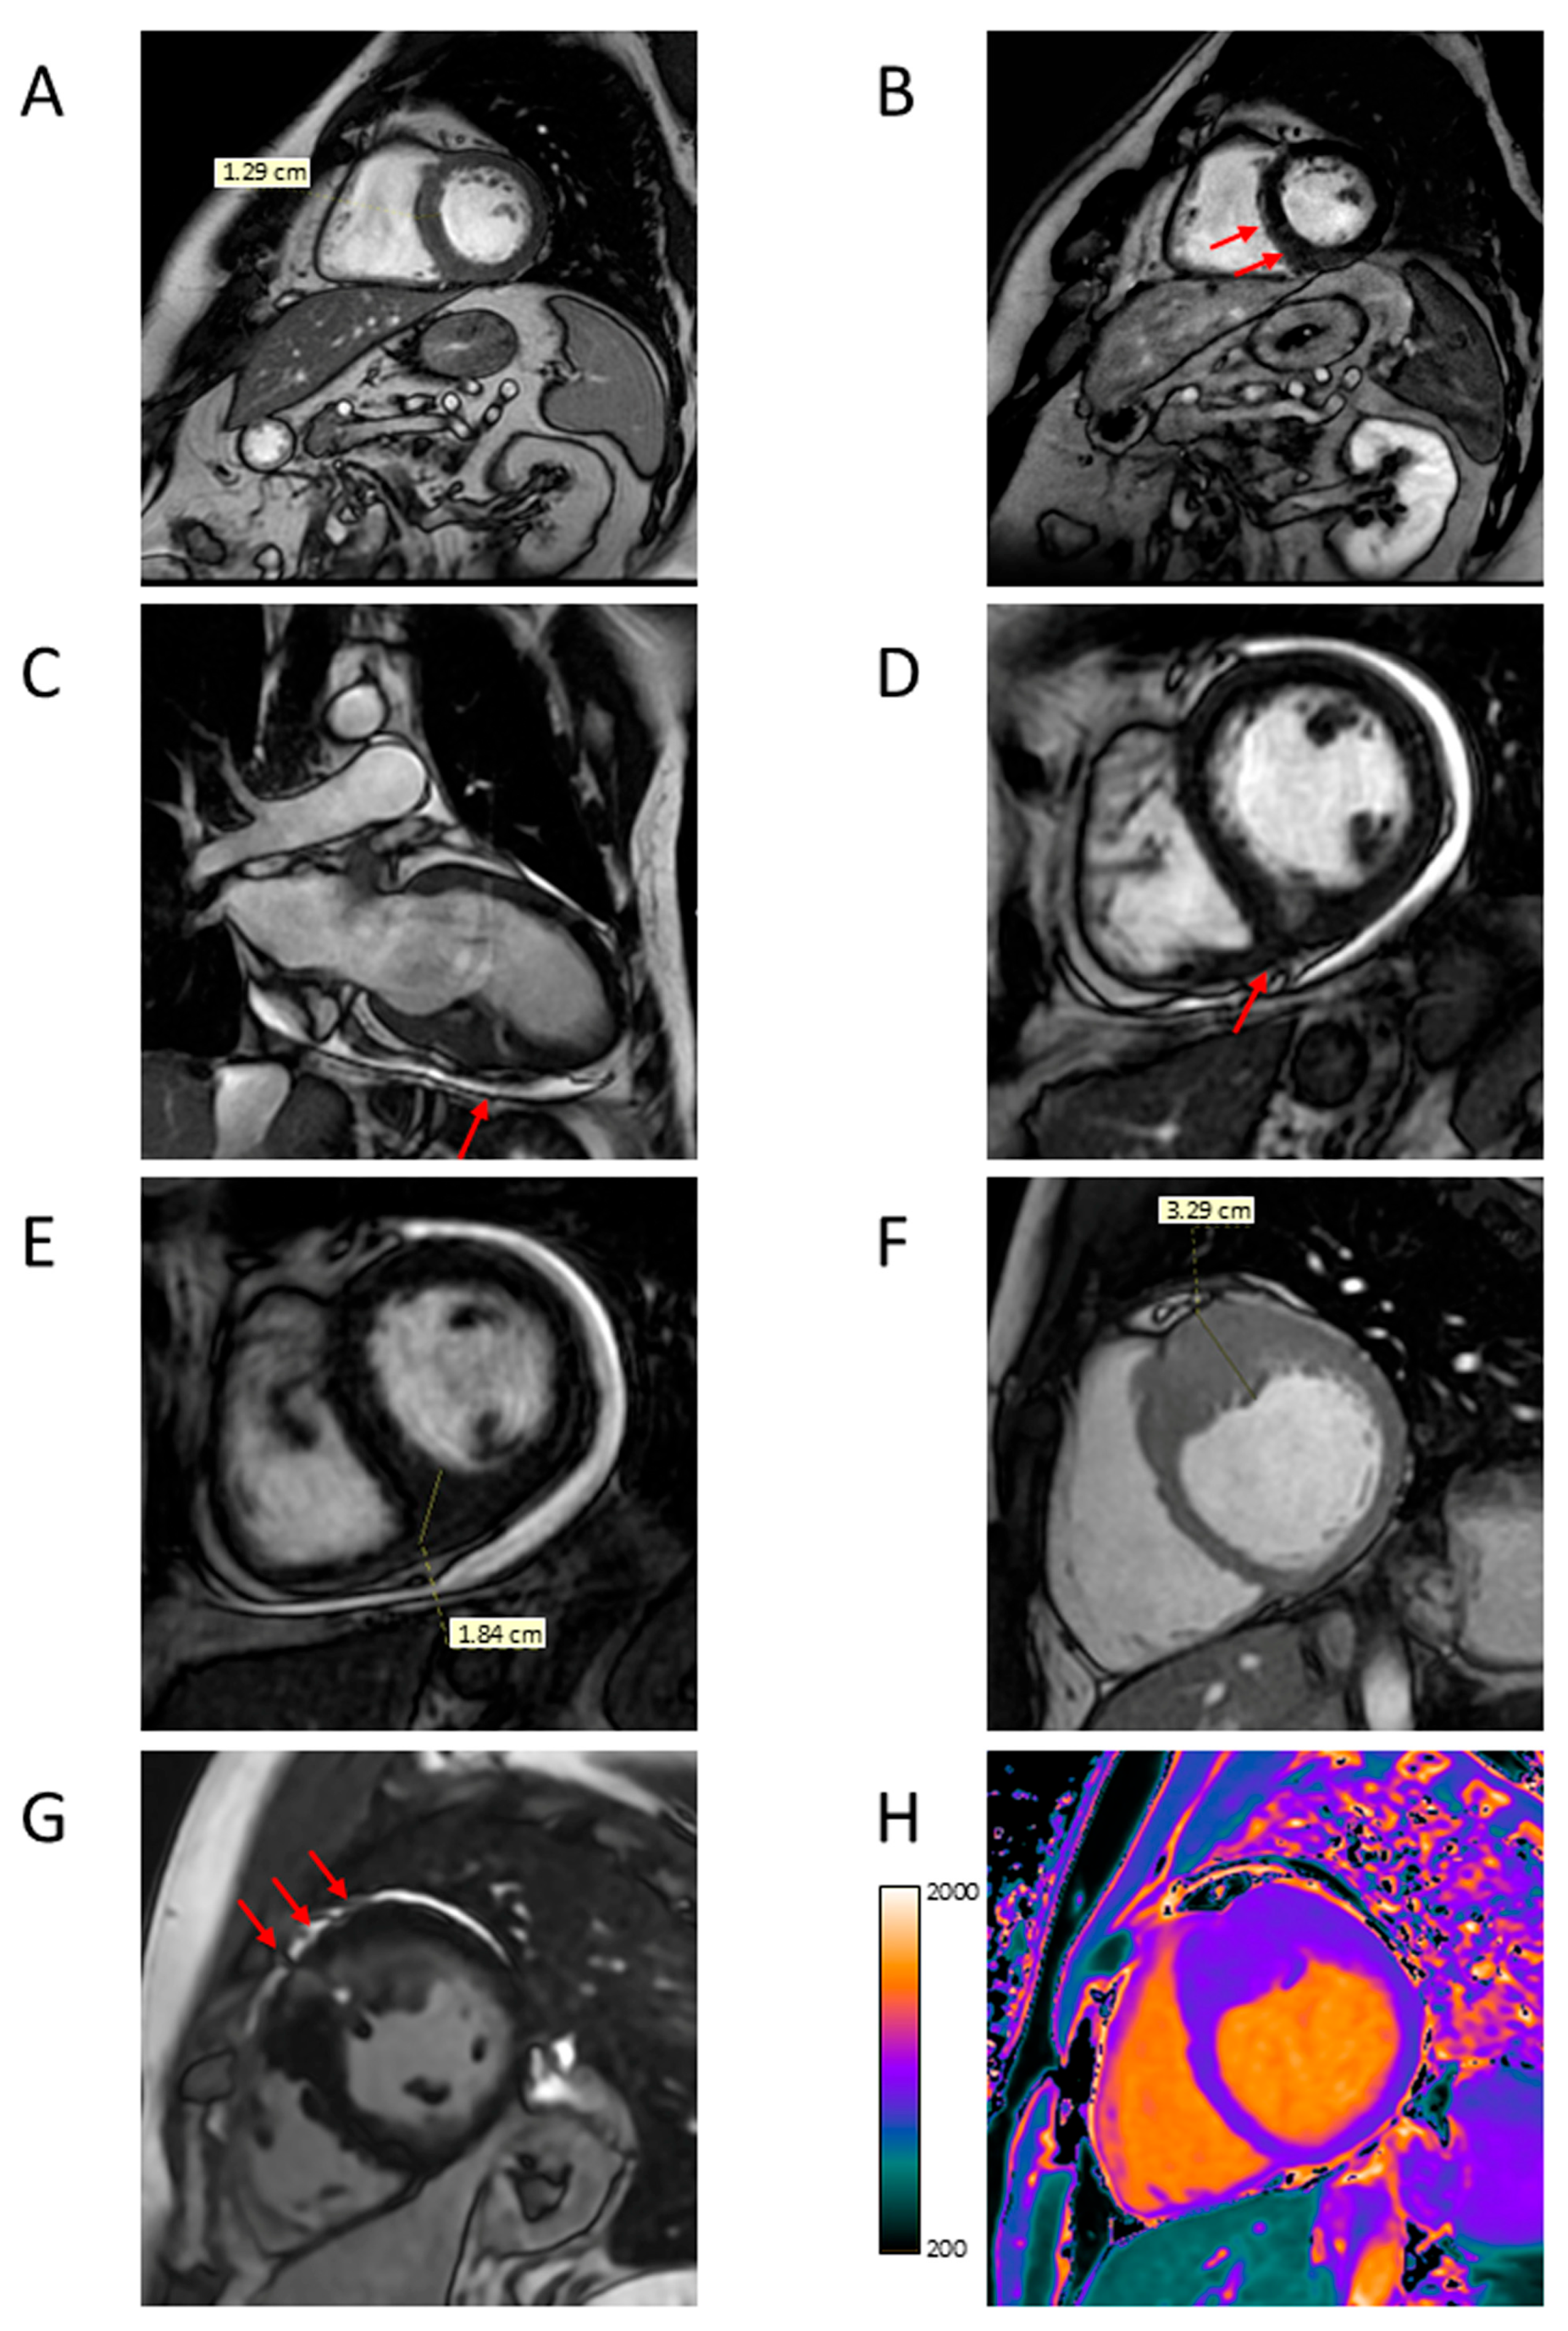

4.2. Apical Aneurysm

4.5. Myocardial Fibrosis

5.2. Characterization of HCM Phenotypes and Risk Stratification